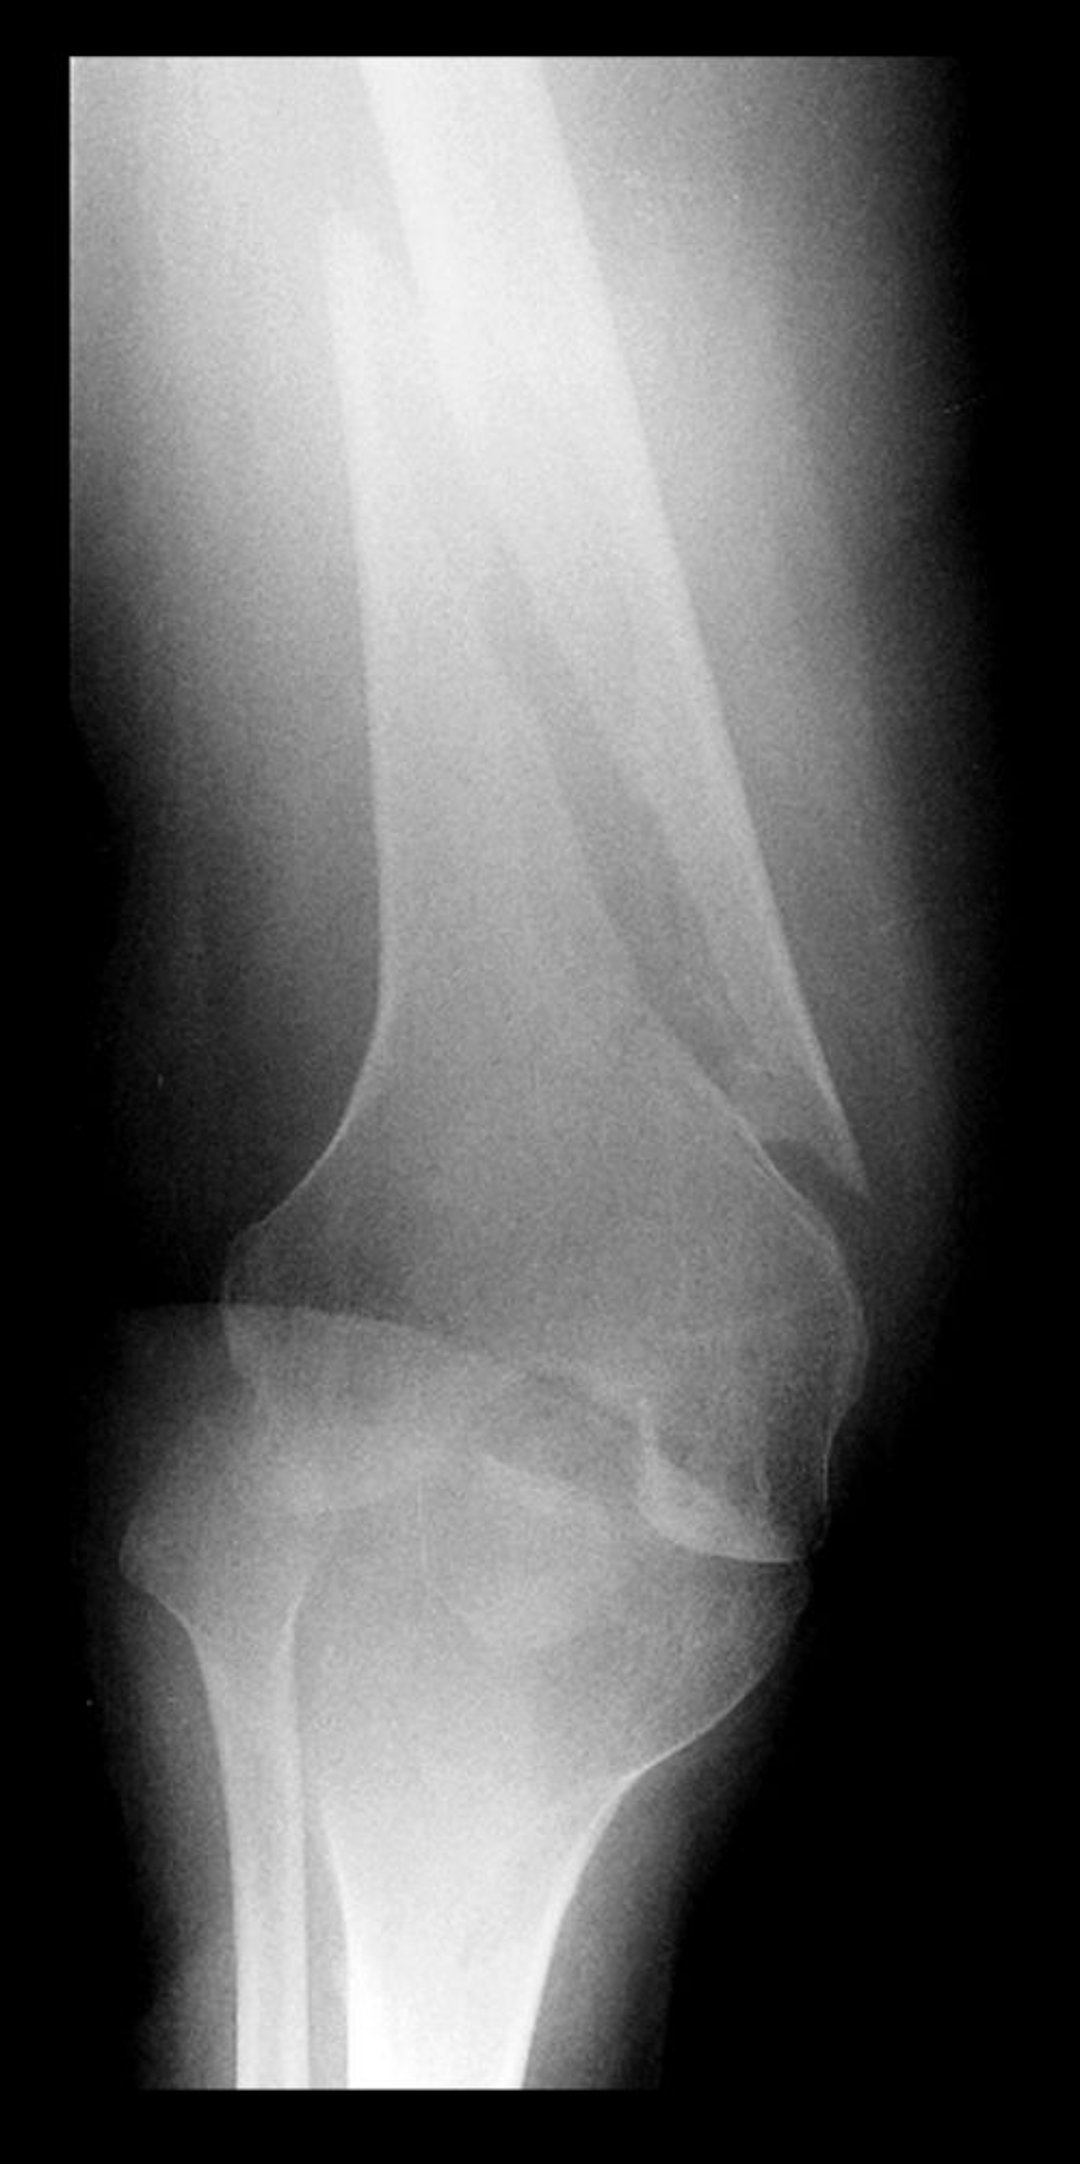

Frattura spirale del femore distale

Questa radiografia del femore distale mostra una radiotrasparenza con una componente parallela all'asse longitudinale dell'osso, indicativa una frattura spirale.